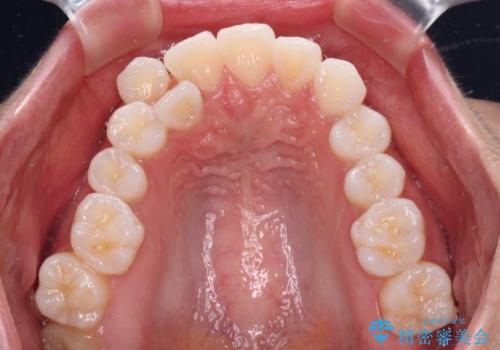

- 八重歯と、それによる正中のズレを気にして来院された患者様です。

口元の突出感は気にしていなかったため、上顎の左右第一小臼歯を抜歯することで、八重歯の解消と上顎の正中を改善していくこととしました。

予定より期間がかかりましたが、上下の正中位置を綺麗に一致させることができました。